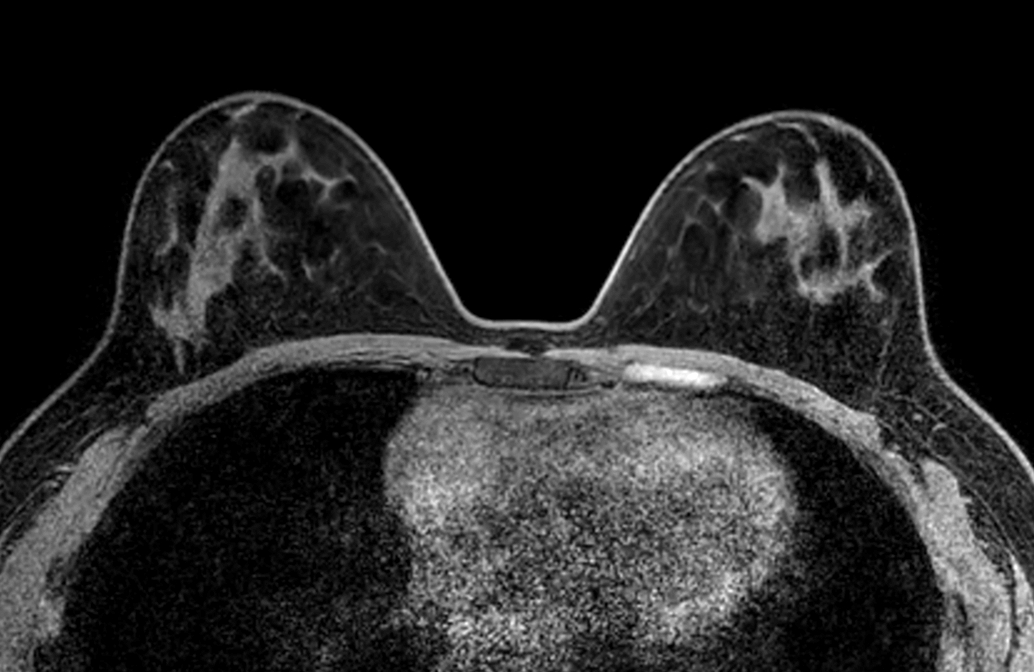

Axial mDIXON XD FFE (Water only) - Dyn 4

Axial mDIXON XD FFE (Fat only) - Dyn 4